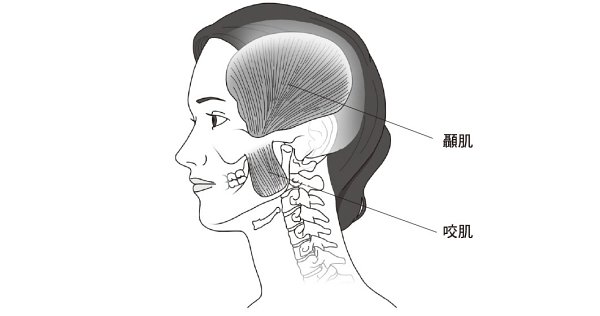

此時最需要的是肌肉的力量,因此心跳會加速,以便向肌肉細胞供給更多的能量和氧氣。接著是緊縮肩膀肌肉、顏面肌肉,尤其是咬緊牙關時使用的下顎肌肉等一系列的肌肉。

處於壓力的情況下,即使本人沒有意識到,肌肉也會不知不覺地緊縮。當肌肉過度緊張的時候,就會出現各種問題。眾所周知,下顎肌過度緊張使得牙關咬得太緊的話,就會造成顳顎關節障礙或睡眠時磨牙的現象。脖頸和肩膀的長期過度緊張會形成烏龜頸(頭部前引),導致頸椎間盤突出或肩關節障礙。慢性壓力會導致身體因為肌肉不必要的緊張而形成不均衡的姿勢,這是許多肌肉骨骼系統疾病的根本原因。我要說的結論可能存在單純化的錯誤,但我認為,一言以蔽之,慢性壓力就是杏仁核長期活要躍的狀態。這種狀態不僅會傷害身體,還會削弱心理肌力。